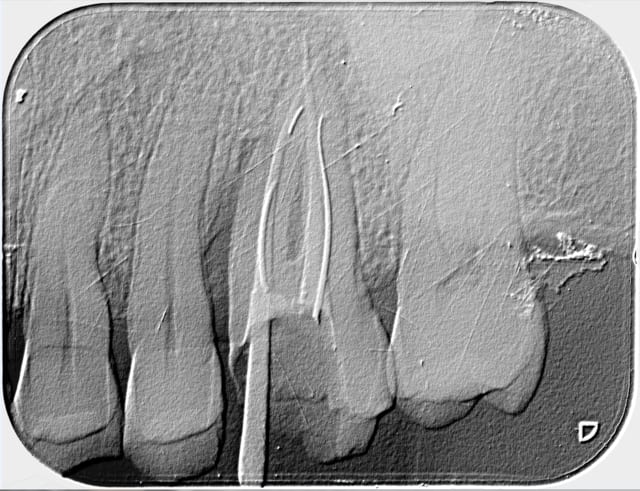

Voici le résultat d'une 3ème séance de recherche du MV 2 le vague à l'âme expliquant l'absence de digue , et mv 2 que j'aurai nommé le CCE pour casse couille endodontique mais n'étant pas endo exclusif je reste courtois avec cette désespérance souvent absente radiologiquement après obturation et dont le trajet incertain me laisse rêveur , quand à la guérison de l'image en mésial prions pour que Saint NaOCl et Saint EDTA veillent sur nous .

Bref cônes d'argent présents MV1 et DV , palatin ?!?!? : aucune image radio , à tout les coups mon MV 2 sera insuffisant et je serai le maillon faible ...)))

Tu remarqueras qu'il n'y a aucune image apicale face aux cônes d'Ag .

Egalement les rapports curieux entre mv1 et mv2 , je suis arrivé à virer le 1/3 milieu du cône qui se trouve dans mv1 et je suis au bout du mv2 que j'ai pénétré facilement après l'avoir cherché 3 séances...